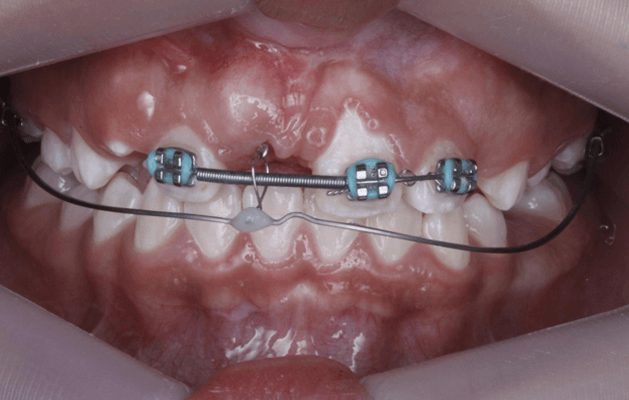

En el siguiente mes se utilizó la técnica de tracción con arco segmentado, donde se utilizaron el arco 0.018 niti superior sujeto a los incisivos superiores 1.2, 2.2 y 2.1 junto con un resorte de espigas cerradas para mantener el espacio entre el 1.2 y 2.1 y el arco de TMA 17 x 25 colocado en los tubos 16 y 26 respectivamente. Se realiza la activación con 100 gramos de fuerza. (Fig 17)

Fig 17. Fotografía de arco segmentado 0.018 para tracción de incisivo central 1.1